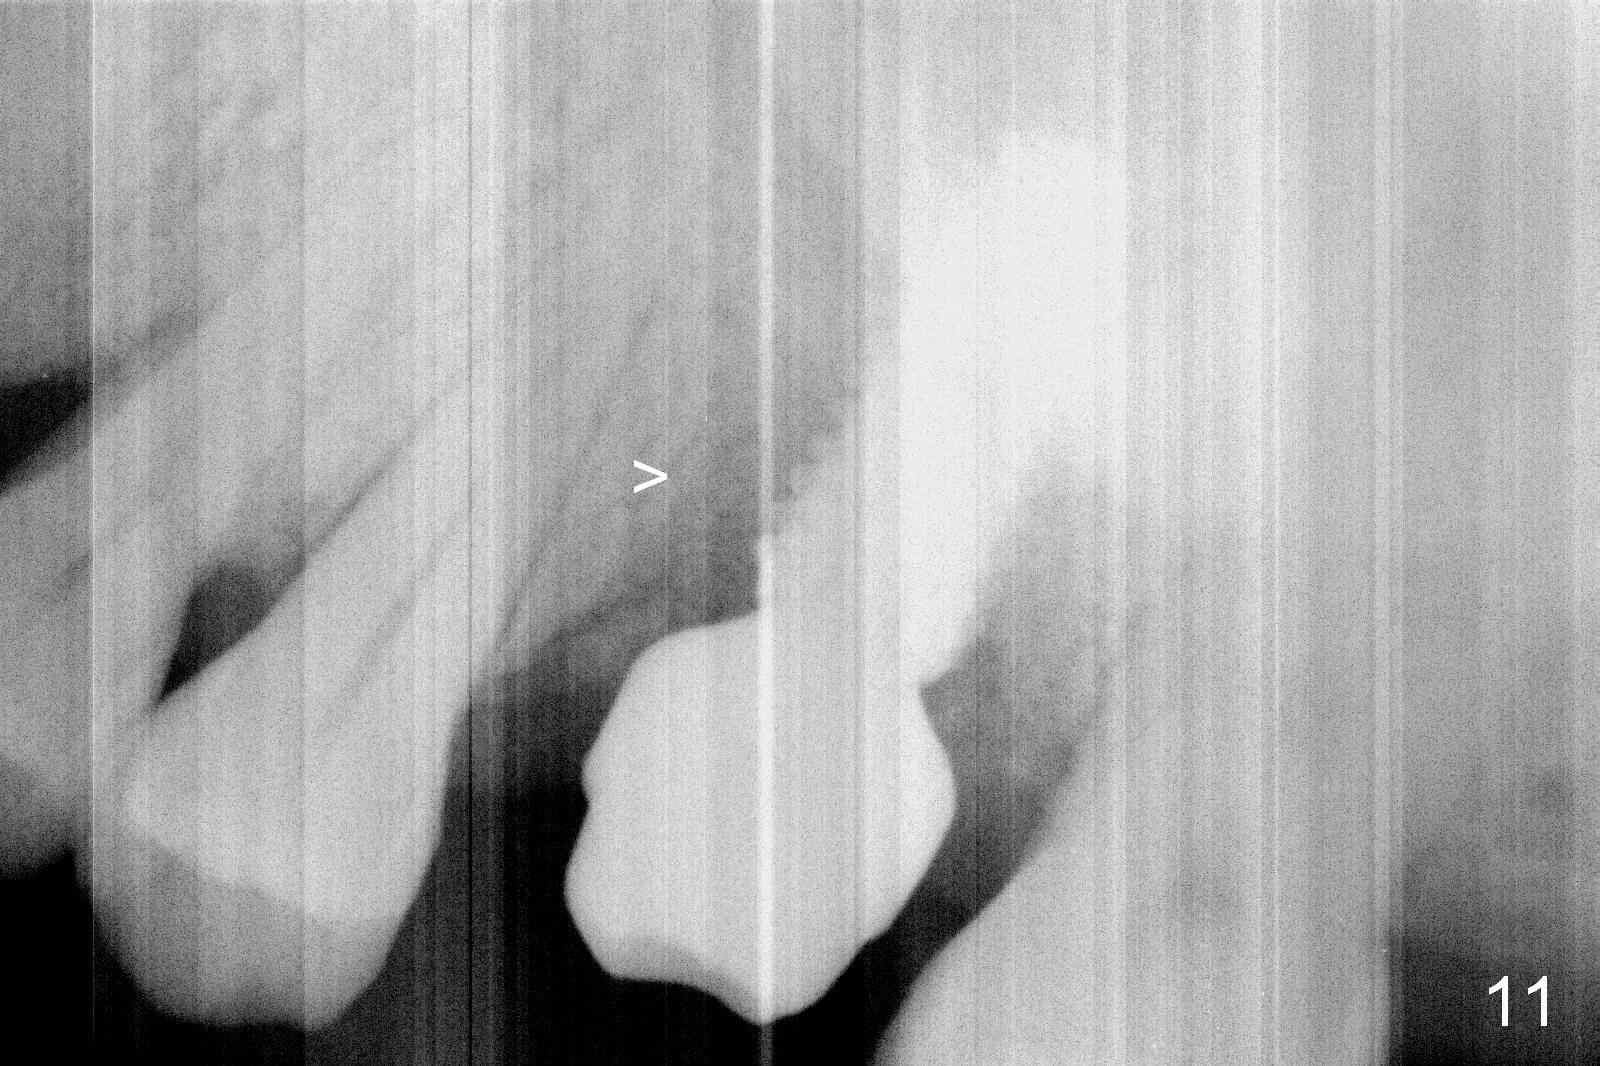

Oral hygiene is excellent postop. The socket heals around the abutment. Four months postop, the native bone appears to be approaching the implant surface (Fig.11 >).